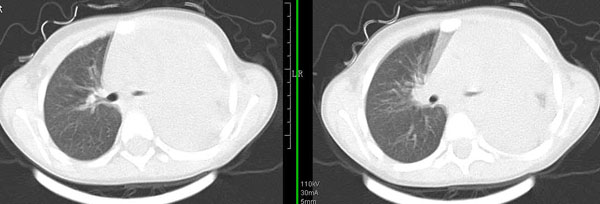

男孩,4岁,发热咳嗽4天。

下面补充ct图片:

此病人是我接手的,发热、咳嗽来做胸透,透视见左侧肺野大部密实,纵隔、心影明显左移,呼吸示纵隔摆动、膈肌矛盾运动(透视下采集了几幅图片),左肺动度明显减弱。询问病人家长,没有吃花生米等呛咳史。由于其影像特征明显,当时诊断:考虑左侧支气管异物并阻塞性肺不张、肺炎。

病人去上级医院支气管镜取出了异物。今天询问上级医院耳鼻喉科主任(是我同学),得知病人异物为胶冻样合并有少许白色粉末,后小儿说晚上喝药片时呛咳过,考虑当时为药片阻塞;另外支气管镜检发现小儿左侧支气管发育略窄,经住院抗炎治疗,现病人基本康复。

多谢各位关注及精彩点评!追踪病人结果时才知道还做过ct检查!对不起!有点晚了,刚刚下载,上传供大家参考!